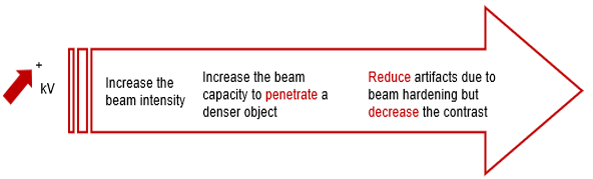

kVp

Increasing the kVp will improve the signal to noise ratio. This increase in beam intensity allows for better penetration of denser objects.

Sufficient high technique is necessary for contrast resolution of soft tissue in the brain and also of large patients who are being scanned for their spine. Reduce artifacts due to beam hardening but decrease the contrast.

Higher kVp means that the photons have higher energies and can penetrate thicker objects.

This image shows the effect of the kVp on image contrast. Note the differences between 100 and 120 kVP. The higher the kVp, the lower the contrast, known as low contrast resolution.

Low contrast detection is used to examine structures with low contrast such as the brain or the abdomen. This is accomplished by using higher kVp.